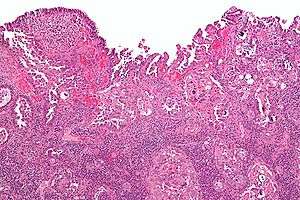

Micrograph of uterine serous papillary carcinoma. H&E stain.

Uterine serous carcinoma (USC), also known as uterine papillary serous carcinoma (UPSC) and uterine serous adenocarcinoma, is an uncommon form of endometrial cancer that typically arises in postmenopausal women.

Histopathologically, uterine serous carcinomas is typically characterized by (1) nipple-shaped structures (papillae) with fibrovascular cores (2) marked nuclear atypia (irregularies in the nuclear membrane, enlarged nuclear size), (3) psammoma bodies and (4) cilia.